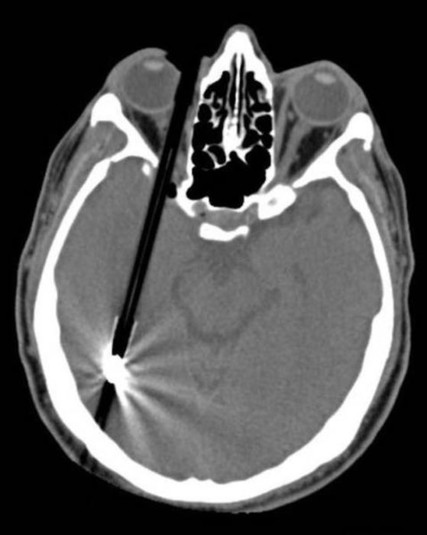

Предметы, которые не очень хочется видеть внутри себя

Под рентгеновскими лучами порой видны не только внутренние органы и кости, но и инородные тела, попавшие в организм

Истории попадания этих предметов в организм могут быть самыми невероятными и запутанными, но больше всего медиков интересует процесс их извлечения, впрочем, в этом заинтересованы и сами пациенты, допустившие нечто подобное со своим телом.